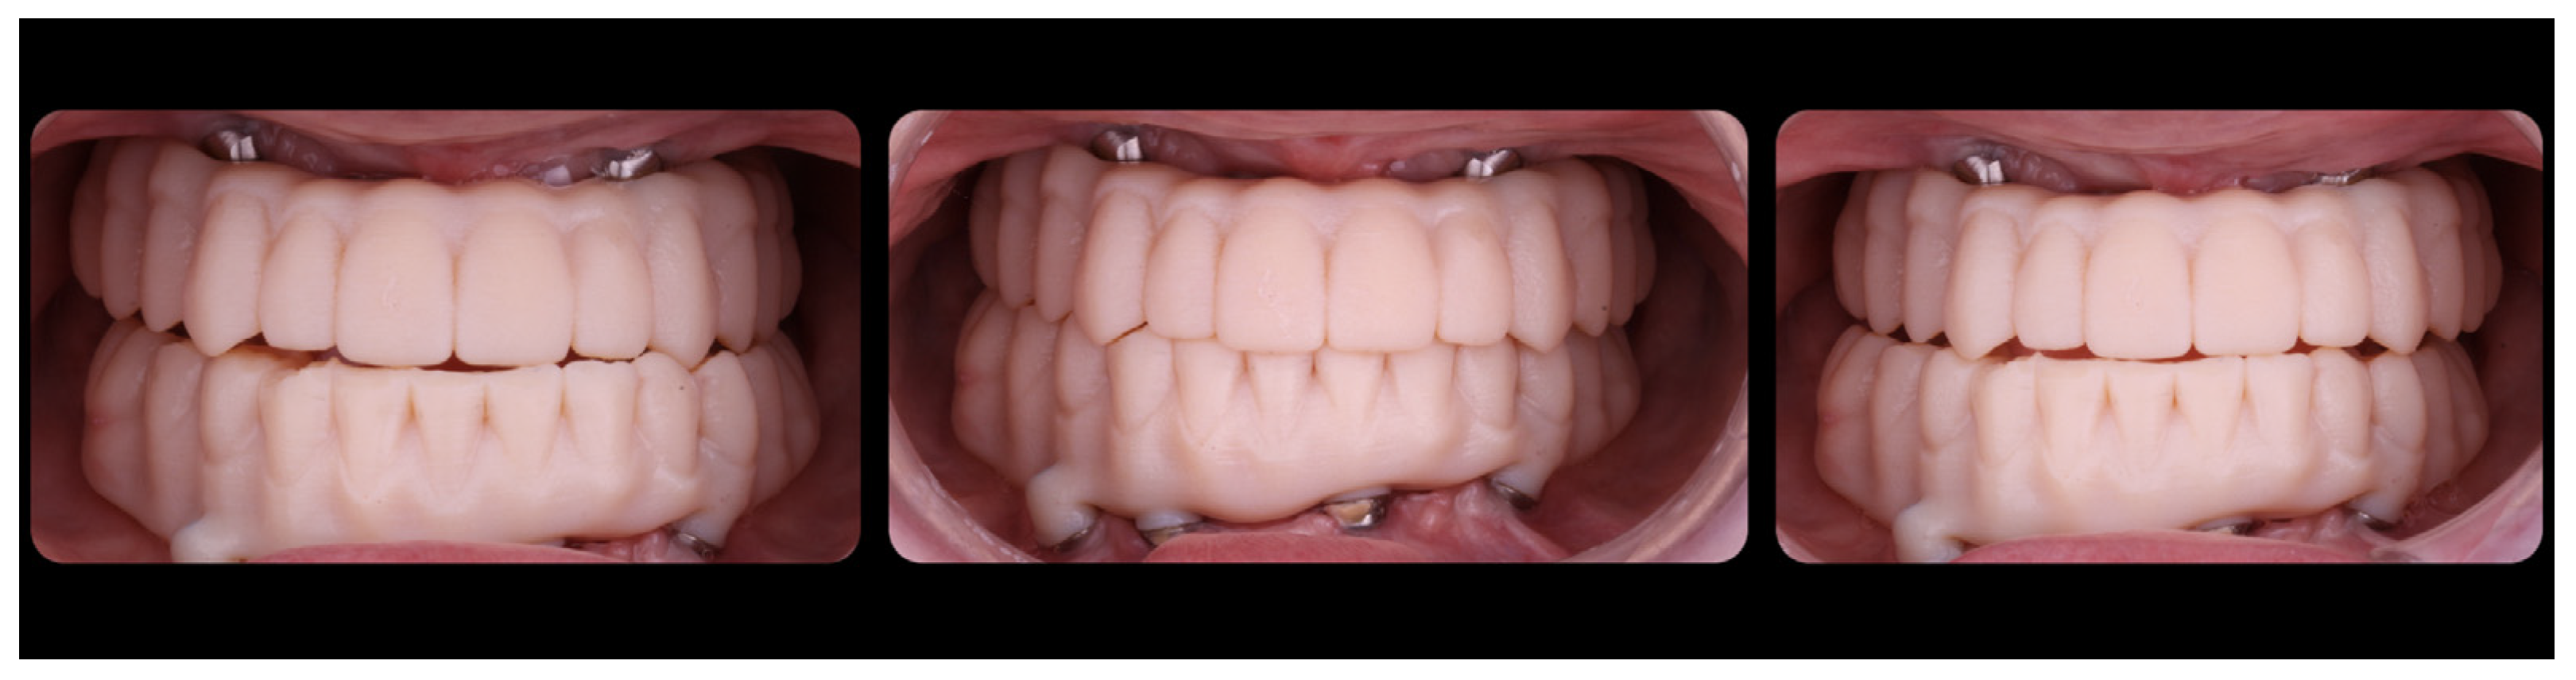

3. Results